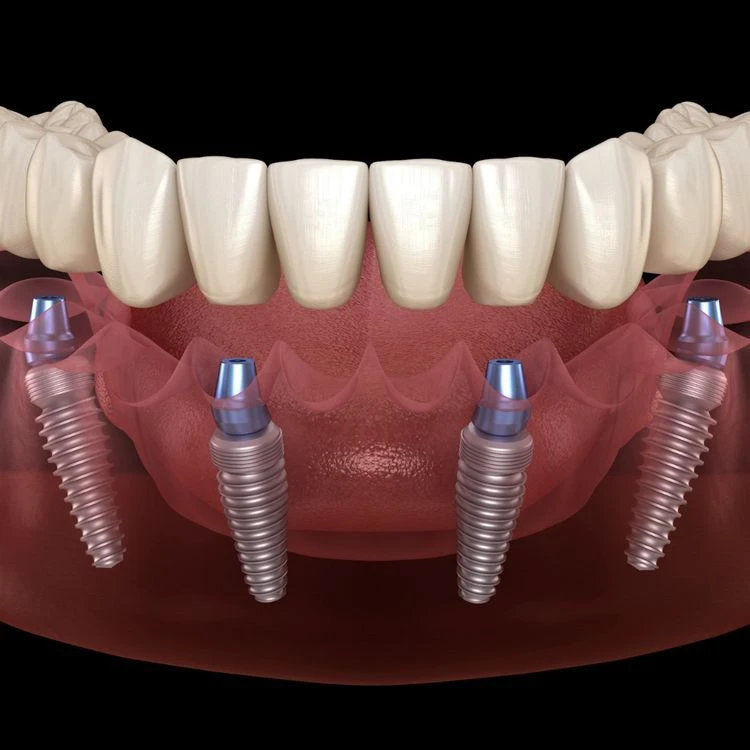

All-on-4 implant tedavisi, tüm dişlerinizi tek seans içerisinde çıkartılıp yerine 4 adet implant üzerine sabitlenen bir köprü ile değiştirmektir. Bu tedavi yöntemi, diş eksiklikleri olan kişilere daha hızlı ve daha kolay bir diş restorasyonu sağlar.

All-on-4 implant tedavisi, bir cerrahi işlemle yapılır. Tedavi sırasında, öncelikle diş etleri kaldırılır ve dişler çekilir. Sonrasında, implantlar çene kemiğine yerleştirilir ve geçici bir köprü takılır. Yerleştirilen implantlar iyileşme sürecinde kemikle kaynaşır ve kalıcı köprü yerleştirilir.